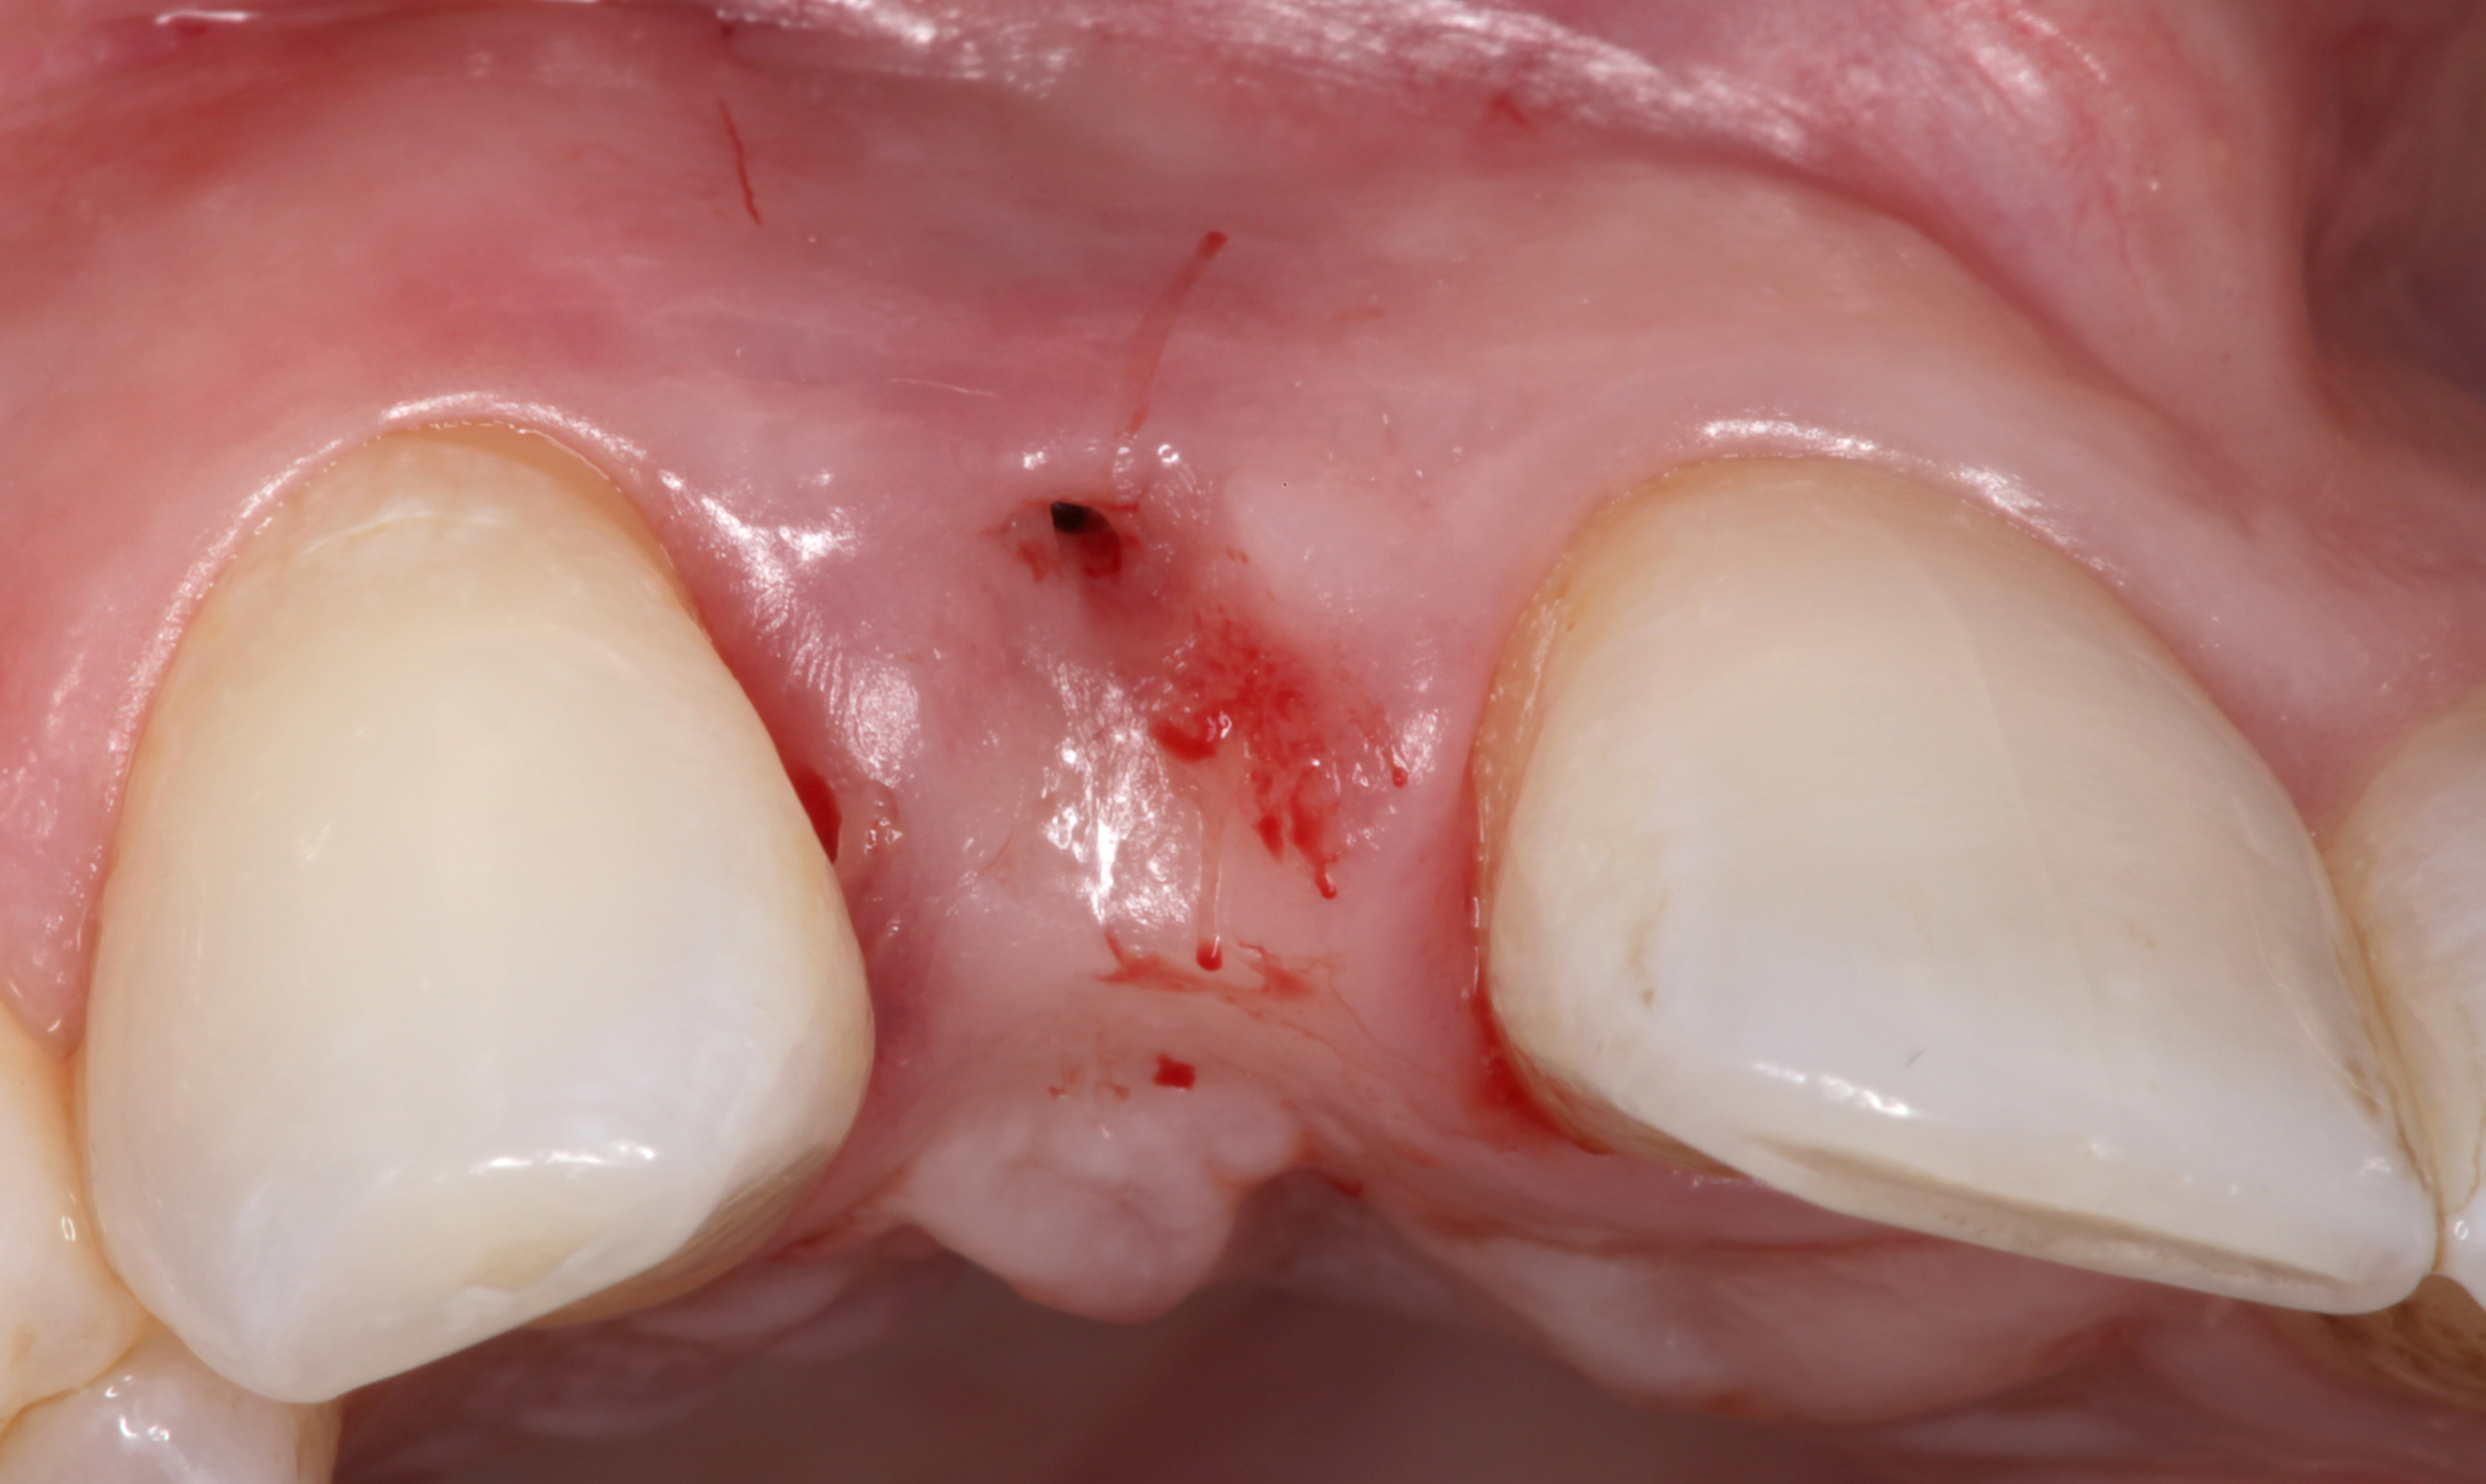

The following case report provides an example of this case scenario: A 24-year-old white male presented with congenitally missing tooth No. 26 restored with a single-tooth cement-retained implant restoration. The implant was placed excessively to the facial aspect of the edentulous site and too shallow, and the periodontal phenotype was thin scalloped (Figure 32). In an effort to mimic the lost midfacial soft tissues, pink ceramics were used as a cosmetic facade. Even though the restoration was not in the esthetic zone, the patient was highly displeased with the esthetic outcome and sought remediation.

The crown and screw-retained custom abutment were removed, and a surgical cover screw was placed into the implant, thereby allowing spontaneous gingival augmentation in situ (Figure 33 and Figure 34). Note that the lingual aspect of the implant site was significantly more coronal than the labial aspect, which was positive because the defect would be limited to a facial–lingual defect. A fixed RBR bridge was cemented on the adjacent teeth and used as a tooth-supported transitional provisional restoration (Figure 35). A few weeks were allotted to let the soft tissue heal and migrate around the cover screw (Figure 36) to see if there would be complete coverage, thereby allowing a soft-tissue augmentation procedure to be performed with primary flap closure as in clinical scenario No. 2. The major obstacle in achieving a positive tissue response was that the implant depth was also deficient because the implant–abutment connection was at the level of the free gingival margin. It was decided that the best treatment option would be to remove the implant. A high-powered reverse-torque device (Fixture Remover Kit, NeoBiotech, www.neobiotechus.com) was used to remove the implant atraumatically (Figure 38 through Figure 41). The implant socket was allowed to heal for several months not unlike an extracted tooth (Figure 42). A new implant was placed in a better position from both a restorative and esthetic perspective (Figure 43), and after a few months of healing, a new crown was made (Figure 44). A satisfactory functional and esthetic result was achieved (Figure 45 and Figure 46) without employing pink porcelain.

Fig 32. A dissatisfied patient presented with significant midfacial recession of implant restoration of tooth No. 26. Pink ceramic material was used unsuccessfully to prosthodontically compensate for the lost midfacial tissue.

Figure 32

Fig 33. Excessive facial angulation of the implant placement shown with an abutment driver in the access screw hole.

Figure 33

Fig 34. A surgical cover screw was placed in an attempt to decoronate the implant and gain soft-tissue coverage in situ.

Figure 34

Fig 36. Two weeks after RBR placement, the soft tissue did not adequately cover the implant. The problem was in poor implant angulation and proper depth to allow the soft tissues to cover over.

Figure 36